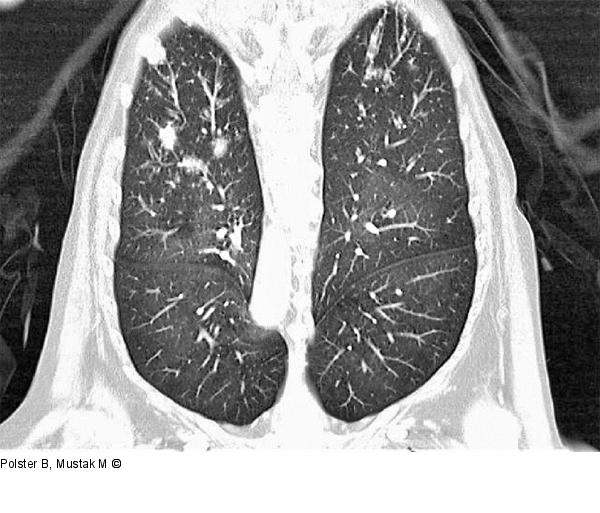

Abbildung 4: Rheumapatienten im OP Kleinherdige Aspergillose (chronische karnifizierende Pneumocystis jirovecii und Aspergillus-Spezies), zusätzlich frischere bakterielle Pneumonie mit Lungenabszessen und nachgewiesener Staph.-aureus-Besiedelung. Bild: KFJ - Zentralröntgeninstitut; CT der Lunge. |